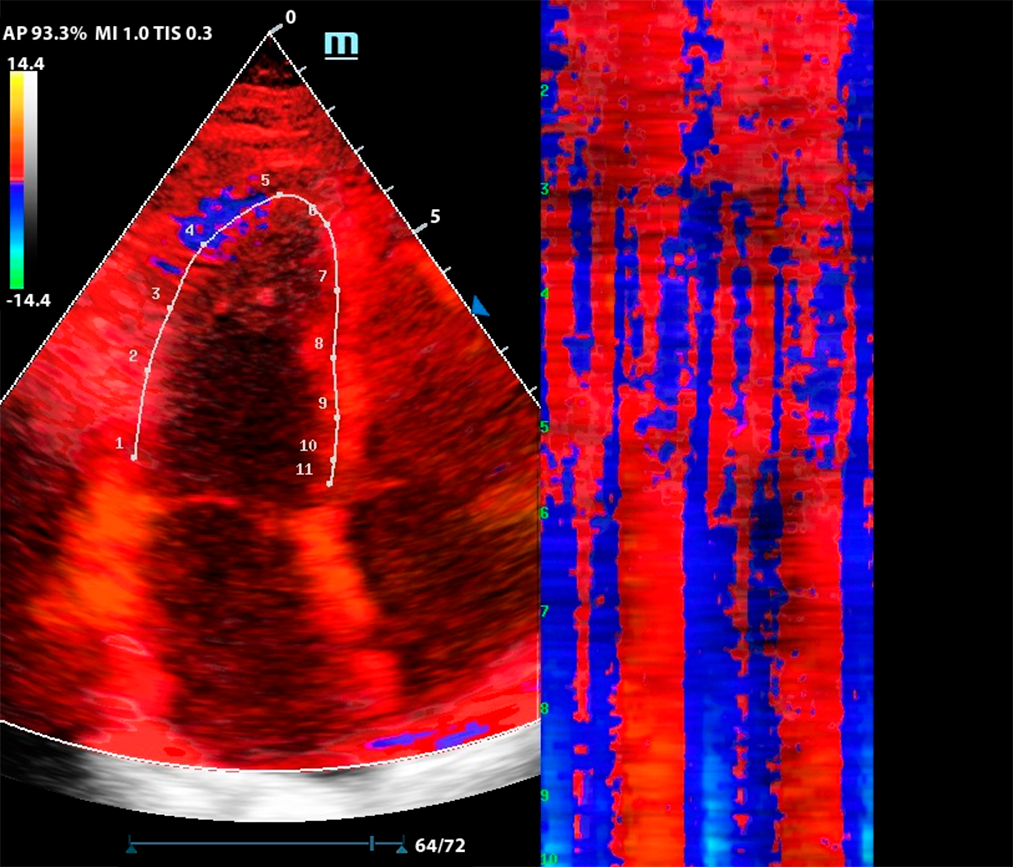

Комбинация функций TDI и Free Xros CM

М-режим — один из наиболее старых методов сканирования. Более современная версия — это свободный М-режим, который также называют Free Xros M. Однако, технология не остановилась на этом и на современных УЗ аппаратах доступен изогнутый М-режим - Free Xros CM.

Функция изогнутого М-режима особенно интересна в комбинации с тканевым допплером (TDI). Оконтуривание миокарда в цветовой карте TDI позволяет оценить кинетику левого желудочка посегментно, в виде цветовой карты на графике Free Xros CM.

Метод разворачивает левый желудочек в плоскую палитру движений за счет окраски тканевого допплера, это позволяет сравнить кинетику в каждом моменте цикла сокращения и расслабления.